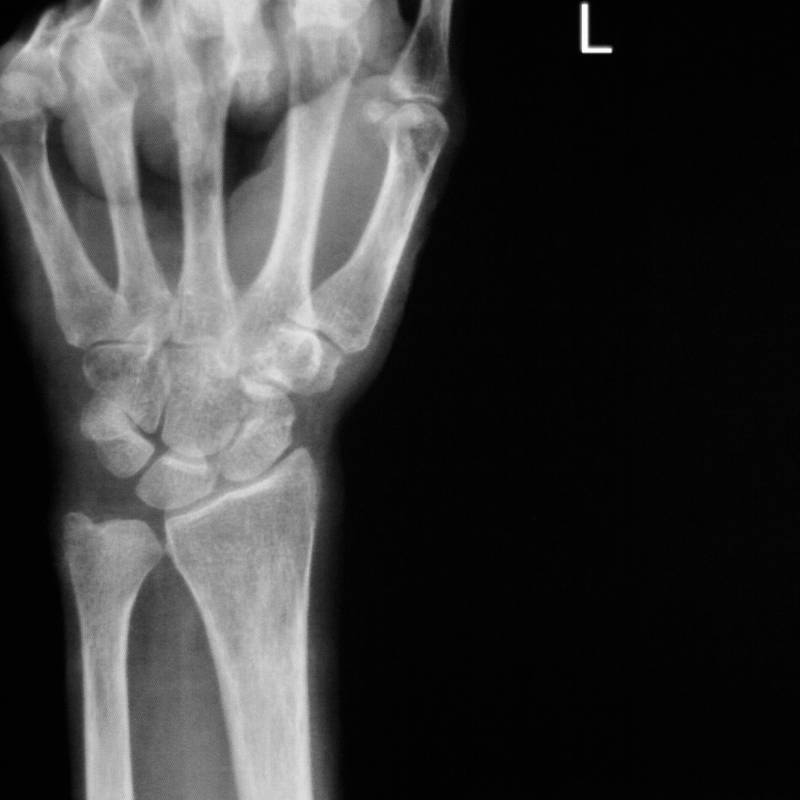

Digunakan untuk mengesan masalah pada pergelangan tangan.